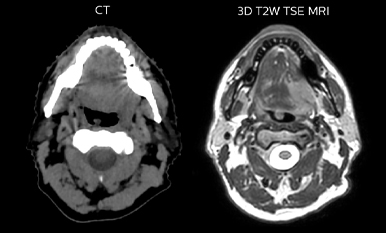

While CT clearly defines bone and cartilage, the modality’s limited soft tissue visualization makes head-and-neck structures often appear virtually indistinguishable from another. Coregistering an MRI dataset as a secondary information source for head-and-neck target and organ at risk (OAR) delineation is vital, according to La Tour’s Dr. Breuneval.

“MRI contributes substantially to visualizing head-and-neck lesions compared to CT and allows a better differentiation of normal from abnormal tissue,” he explains. “Tumor edges and extracapsular lymph node extension – as well as OARs, such as parotid glands, pharyngeal muscles and the brachial plexus – are better depicted. The resulting benefit is that tumor margins may be reduced and OARs better spared.”

Comparison of CT simulation scan

Comparison of CT simulation scan (left) and T2W 3D MRI (right)